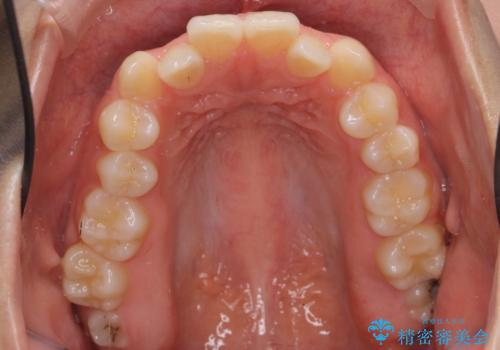

前歯、奥歯ともに反対咬合になっており、また上顎の前歯が少し突出気味でした。

上下左右の小臼歯を抜歯しています。

臼歯の反対咬合は簡便なマウスピース矯正で治すのは難しいです。